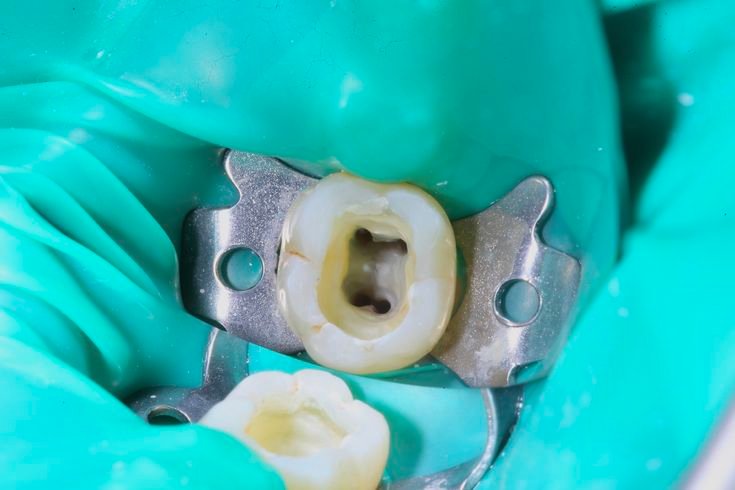

3. Intervento Endodontico Indolore

Dopo l’anestesia e l’isolamento del dente con la “diga di gomma” per operare in sicurezza, procediamo alla pulizia e disinfezione dei canali.